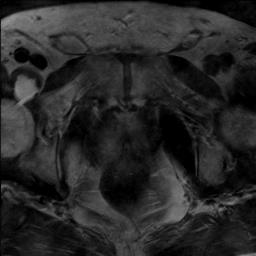

Modern deep neural networks struggle to transfer knowledge and generalize across diverse domains when deployed to real-world applications. Currently, domain generalization (DG) is introduced to learn a universal representation from multiple domains to improve the network generalization ability on unseen domains. However, previous DG methods only focus on the data-level consistency scheme without considering the synergistic regularization among different consistency schemes. In this paper, we present a novel Hierarchical Consistency framework for Domain Generalization (HCDG) by integrating Extrinsic Consistency and Intrinsic Consistency synergistically. Particularly, for the Extrinsic Consistency, we leverage the knowledge across multiple source domains to enforce data-level consistency. To better enhance such consistency, we design a novel Amplitude Gaussian-mixing strategy into Fourier-based data augmentation called DomainUp. For the Intrinsic Consistency, we perform task-level consistency for the same instance under the dual-task scenario. We evaluate the proposed HCDG framework on two medical image segmentation tasks, i.e., optic cup/disc segmentation on fundus images and prostate MRI segmentation. Extensive experimental results manifest the effectiveness and versatility of our HCDG framework.